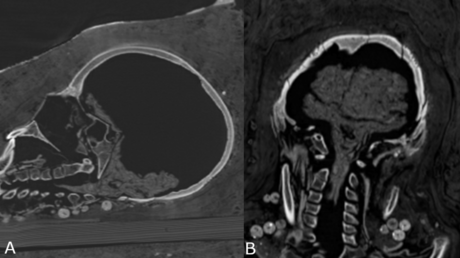

Mediante análisis de tomografía computerizada, los investigadores lograron obtener información sobre el estado de conservación de los cuerpos, la técnica de momificación artificial usada, la edad de los individuos en el momento de la muerte, así como su género, altura y salud.

"Las investigaciones radiológicas anteriores de las momias de los períodos romanos ya revelaron que algunas no mostraban evidencia de extirpación del cerebro y de los intestinos. La identificación del cerebro conservado en el caso de la mujer joven apoya, por lo tanto, esta idea", explicó a IFLScience, el investigador principal del estudio, Stephanie Zesch.

Este nuevo tratamiento fue posible identificarlo solo en la momia joven, pues los cuerpos del hombre y la otra mujer estaban "bastante mal conservados" y no se pudo determinar una técnica específica de momificación artificial.